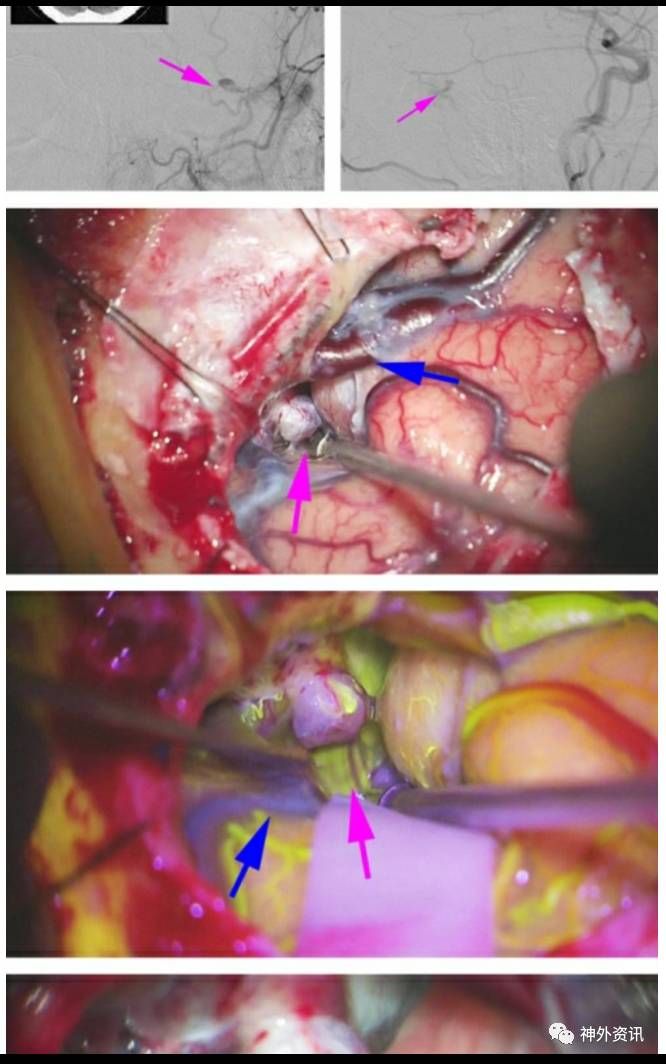

图2. 一例右侧筛骨dAVF(左图,箭头),位于前筛板水平。行右侧眉弓眶上开颅,暴露引流静脉(右图,箭头)。在大脑镰旁发现动脉化静脉,烧灼后离断。

图5. 前后位和侧位颈外动脉血管造影(顶行)提示左侧天幕dAVF(箭头),由硬脑膜中动脉分支供血。幕上动脉化皮层静脉在颞叶后部形成小的曲张静脉。该曲张静脉最终引流至左侧横窦。颞叶后方开颅,暴露动脉化静脉,位于天幕后方(第二行,紫色箭头)。蓝色箭头所示为Labbe静脉。术中荧光造影显示引流静脉早期显影(第三行,紫色箭头),而此时其他皮层静脉(蓝色箭头)还未显影。在天幕靠近瘘的出口、曲张静脉附近,用血管夹阻断瘘口(底行)。